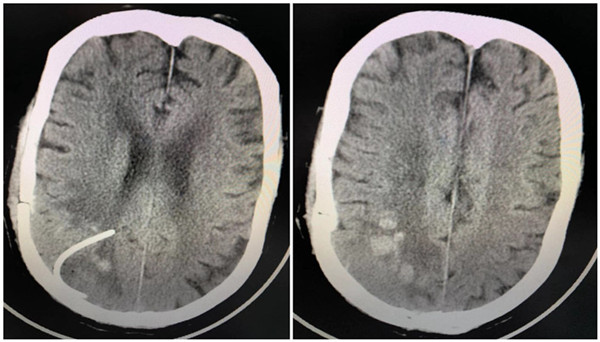

术后头颅CT

手术由巩守平教授主刀、许刚副主任医师、僧志远住院医师协助,薛荣亮教授、藤云鹏主治医师麻醉。手术有条不紊,首先通过电磁导航确定手术切口,然后宋琴主管护师留置电生理电极,打开硬脑膜后行脑表超声确定病变位置,再行皮层翻转确定中央前后回的位置,确定位置后,巩守平教授并未在距离病变最近的皮层切开脑组织,而是先在非功能区造瘘后由非功能区逐渐进入病灶。病变血供丰富,巩守平教授在显微镜下通过娴熟的显微外科技术,一点一点的仔细切除,最终病变被完全切除。